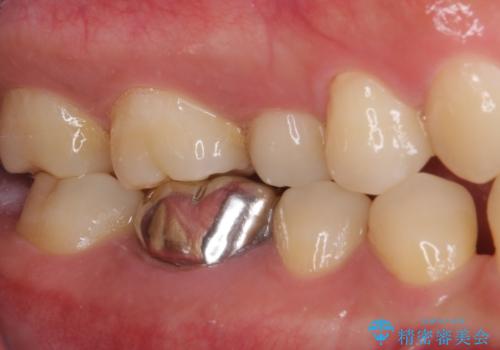

- 口を開けたときに目立ってしまう銀歯をセラミックに替えたいとのことで来院された患者様です。

以前むし歯治療を受けたときは時間がなかったため、近医で銀歯を入れたようですが、周囲の目線が気になるとのことでフルジルコニアクラウンにて補綴することとしました。